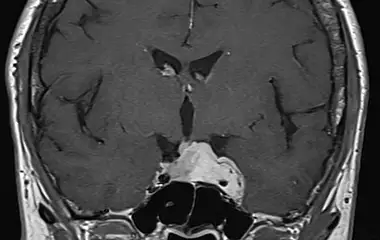

Die komplexe Anatomie und Nähe zu lebenswichtigen Strukturen sowie den wichtigen Steuerungszentralen der Hormone machen Erkrankungen der Schädelbasis stellen besondere Anforderungen an Diagnostik und Therapie. Als Teil des interdisziplinären zertifizierten Schädelbasiszentrums am Uniklinikum Augsburg besitzt die Klinik für Neurochirurgie eine große Expertise im gesamten Spektrum der operativen Therapie an der Schädelbasis. Dazu gehören Schädelbasistumoren wie Meningeome, Schwannome (Vestibularisschwannome), Hypophysentumore, Vaskuläre Dekompression bei Gefäß-Nervenkonflikten (Trigeminusneuralgie) sowie die Versorgung komplexer Schädelbasisfrakturen.

Seltenere Tumore sind Kraniopharyngeome, Chordome, Chondrosarkome, Metastasen oder Gefäßmalformationen. Zudem können Tumor aus dem Nasen- und Mittelgesichtsbereich die Schädelbasis infiltrieren (z.B. Karzinome, Ästhesioneuroblastome)

Die Behandlung von Pathologien erfordert Erfahrung, Präzision, interdisziplinäre Zusammenarbeit mit den Kliniken für Hals-Nasen-Ohrenheilkunde, Neuroradiologie, Endokrinologie und Strahlentherapie. Oberstes Ziel ist die Sicherheit der Patientinnen und Patienten. Dazu gehört auch zu wissen, wann man nicht weiter gehen kann. Wir nutzen die neueste Technik um diese Ziele zu erreichen. So führen wir unsere Operationen mikrochirurgisch oder unter Zuhilfenahme eines Endoskops durch. Die Planung erfolgt bereits vor der Operation und kann mittels Neuronavigation wie geplant durchgeführt werden. Zur Schonung der Nerven und wichtiger Strukturen setzen wir routinemäßig das intraoperative Neuromonitoring ein um in Echtzeit während der Operation drohende Schädigungen zu erkennen und zu vermeiden.